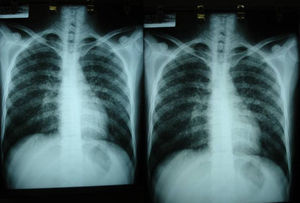

Las pruebas de imagen pueden no ser positivas en los pacientes con histoplasmosis diseminada. Sin embargo, es importante señalar que H. capsulatum se ha aislado de los pulmones de pacientes con sida, por lo que su negatividad no excluye la enfermedad. Se utilizan fundamentalmente para determinar el grado de extensión de la enfermedad (fig. 6).